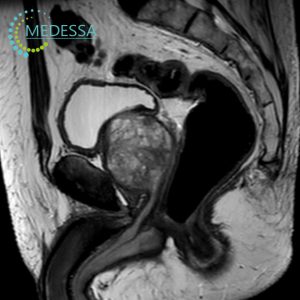

Rectal MRI

- Blood in stool or bowel habit changes.

- Anal or rectal discomfort.

- Suspected tumors or polyps.

- Cancer staging and assessment.

- Preoperative planning.